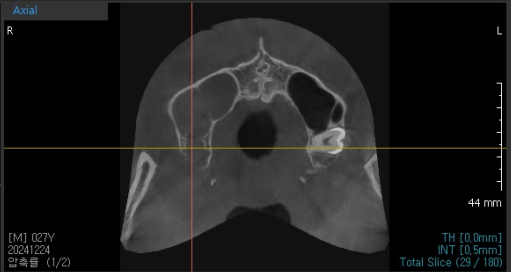

241224 왼쪽과 오른쪽 색깔 차이가 나죠??? 오른쪽 부분은 염증으로 뿌옇습니다.